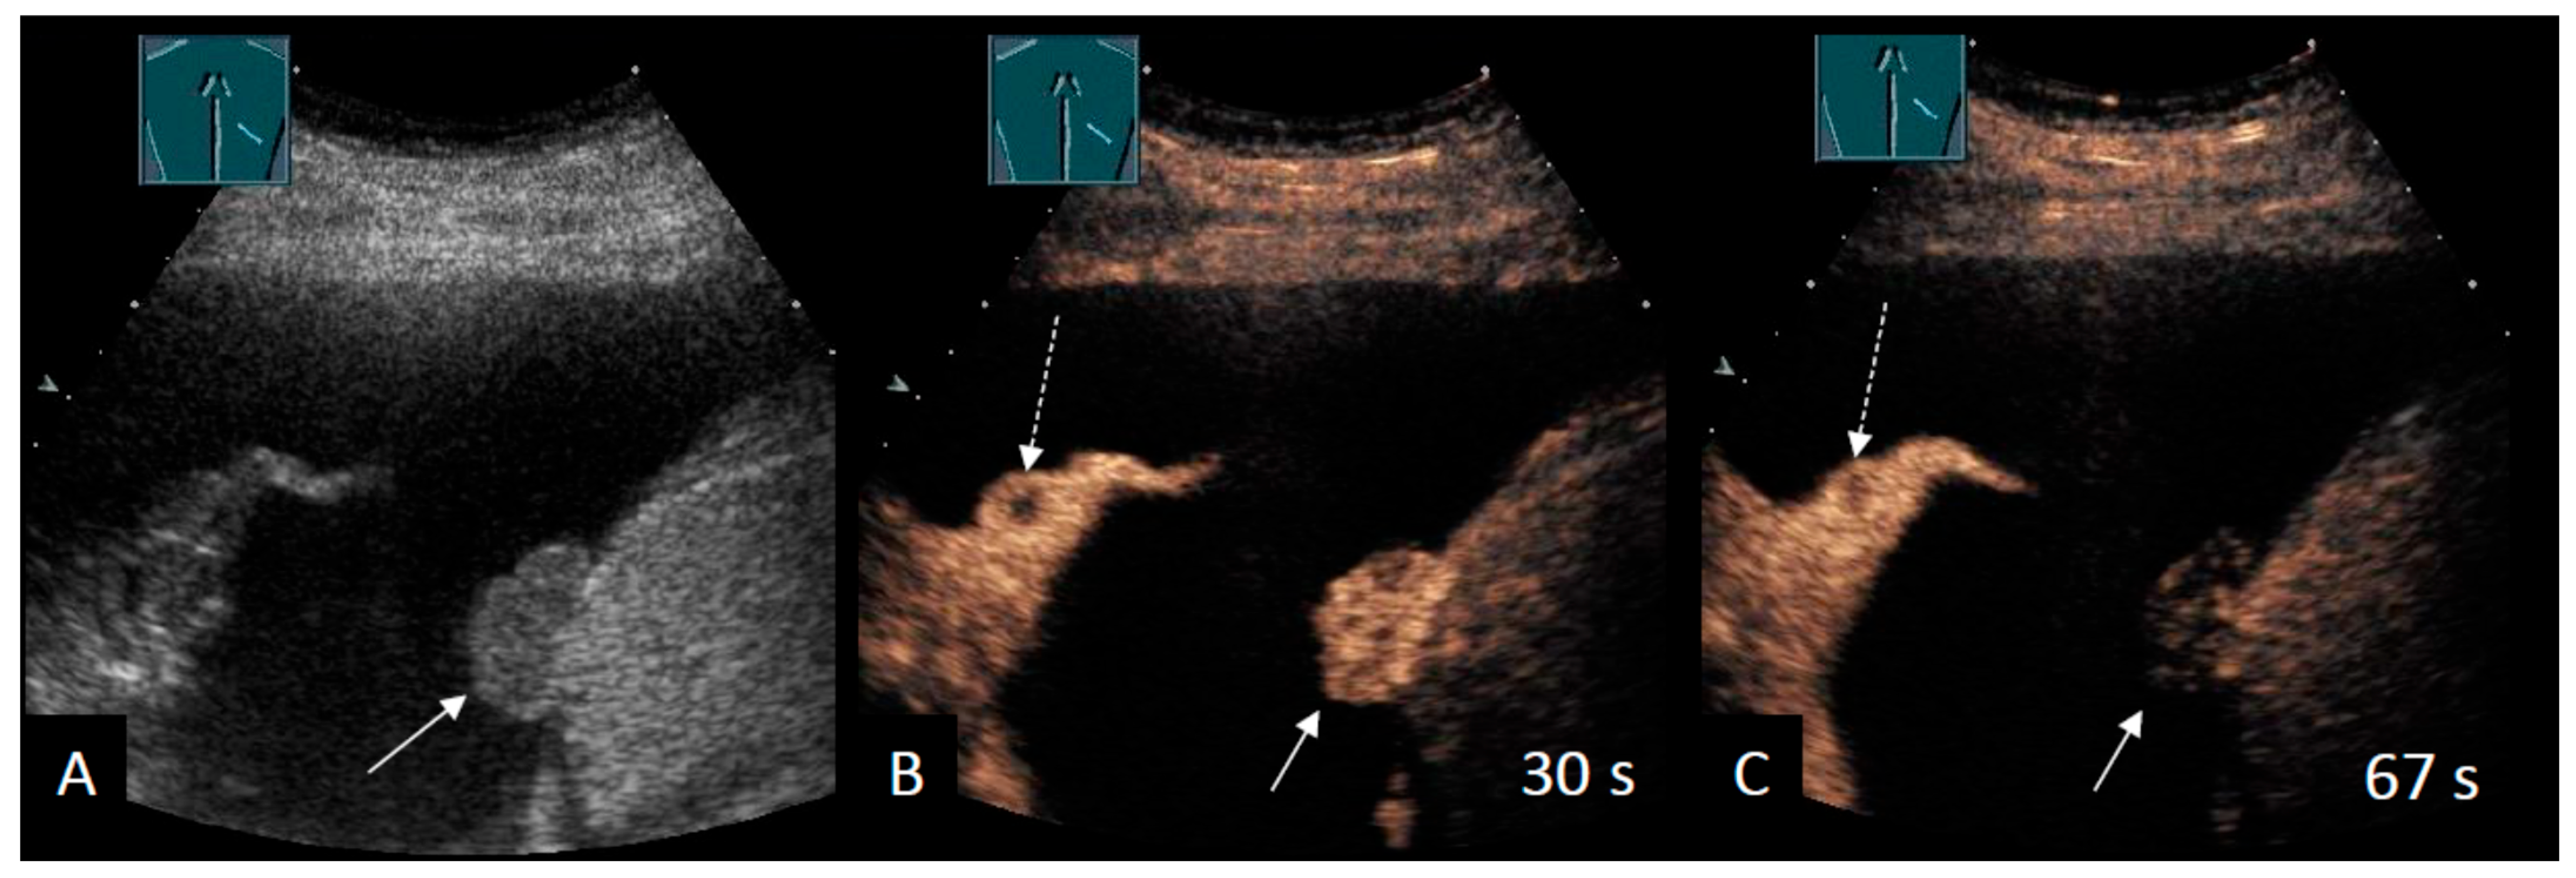

2.4. Intrapulmonary Lesions

Additional Ultrasound Techniques

| CEUS | ||||

| Safai Zadeh et al. [53] | 2021 | n = 83, single-center, retrospective study | To evaluate the value of CEUS in differentiating malignant from benign PE | Sensitivity B-mode: 69.1% Specificity B-mode: 58.5% Sensitivity CEUS: 73.8% Specificity CEUS: 70.7% Subgroup (cytological negative, high risk for MPE): Sensitivity CEUS: 92.3% Specificity CEUS: 90.0% |

| Findeisen et al. [56] | 2022 | n = 63, single-center, retrospective study | To describe the value of CEUS for the differentiation of malignant from benign parietal pleural lesions (Pleural effusion in 50.8%) | Sensitivity CEUS: 92% Specificity CEUS: 54% |

| Yang et al. [58] | 2022 | n = 50, single-center, prospective study | To investigate the diagnostic capabilities of B-mode LUS and CEUS in terms of differentiating between benign and malignant pleural diseases | Multivariate logistic regression: Sensitivity 93.3% Specificity 90.0% |